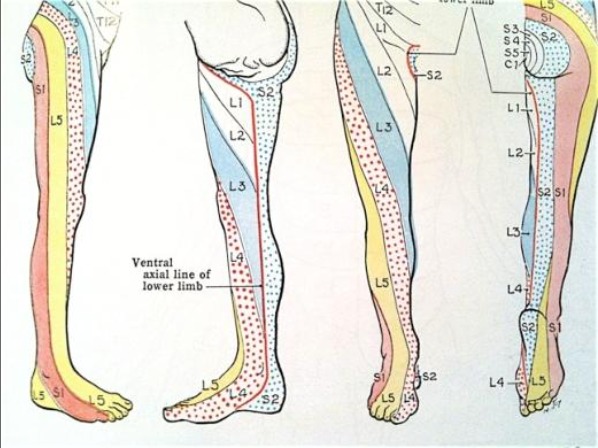

Diagrams courtesy of Netter's Anatomy

Pain in the big toe when due to peripheral neuropathy, may only be located on the inside part of the big toe, (letter A) and going up the inside portion of your leg towards your knee. (letter A) Dermatome chart courtesy of Grant’s Atlas of Anatomy. Order Grant Atlas of Anatomy at Barnes & Noble